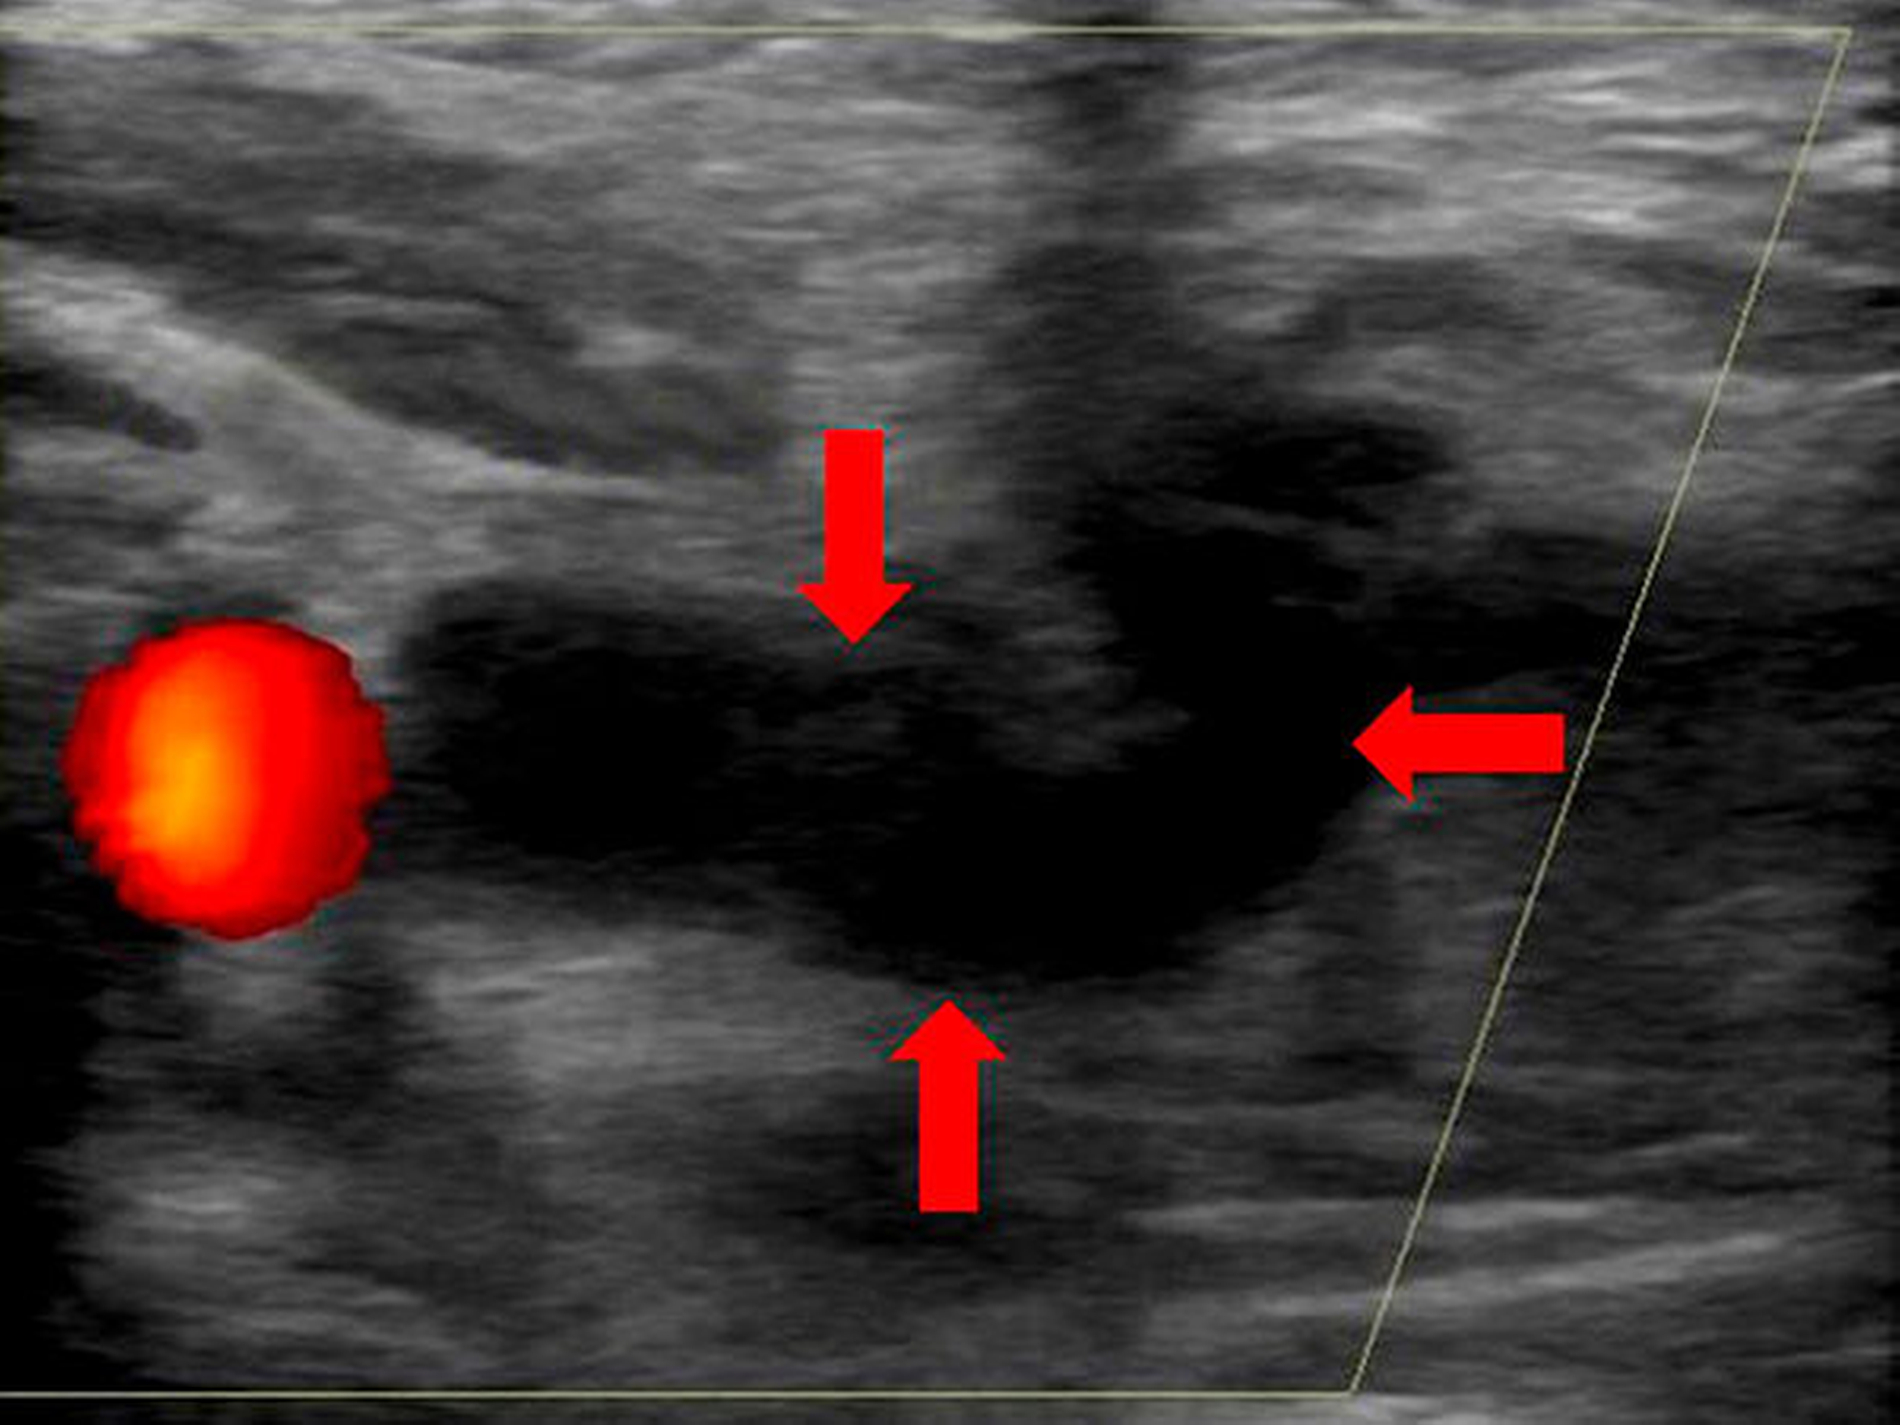

Aufgrund des initialen klinischen Abszessverdachts sowie der erhöhten laborchemischen Entzündungsparameter wurde eine intravenöse antibiotische Therapie mit Unacid 3 g 3 x täglich begonnen. Es erfolgte eine konsiliarische Vorstellung bei den Kollegen der Angiologie. Die durchgeführte Farbduplexsonografie zeigte eine nicht-frische Thrombose im gesamten Verlauf der rechtsseitigen V. facialis, V. retromandibularis sowie der V. jugularis interna (Abbildung 4). Eine Genese im Rahmen der vorbekannten Neurofibromatose wurde diskutiert. Die durchgeführte transthorakale Echokardiografie zeigte keine pathologischen Befunde.